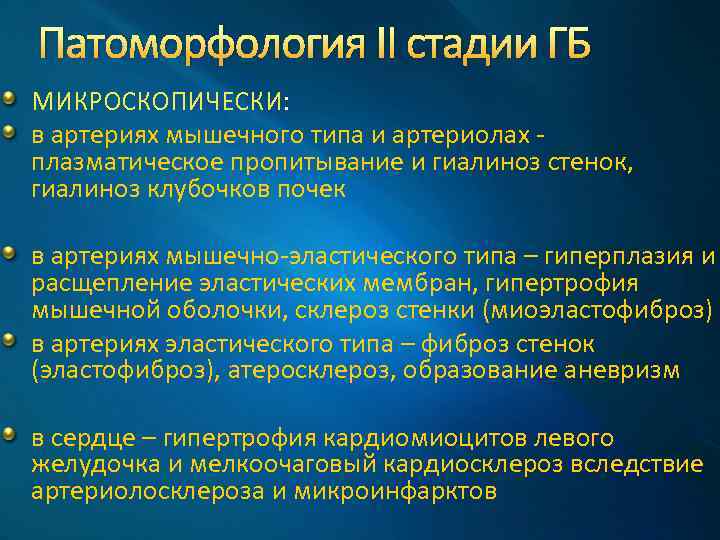

Патоморфология II стадии ГБ МИКРОСКОПИЧЕСКИ: в артериях мышечного типа и артериолах плазматическое пропитывание и гиалиноз стенок, гиалиноз клубочков почек в артериях мышечно-эластического типа – гиперплазия и расщепление эластических мембран, гипертрофия мышечной оболочки, склероз стенки (миоэластофиброз) в артериях эластического типа – фиброз стенок (эластофиброз), атеросклероз, образование аневризм в сердце – гипертрофия кардиомиоцитов левого желудочка и мелкоочаговый кардиосклероз вследствие артериолосклероза и микроинфарктов